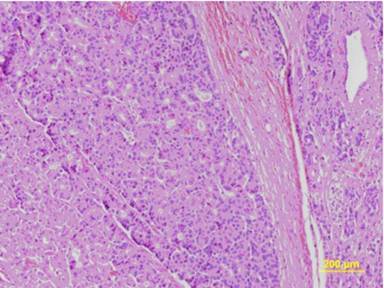

In December 2009, the patient underwent a pylorus-preserving pancreaticoduodenectomy. Histopathological examination showed an acinar cell carcinoma with angiolymphatic invasion and infiltration of the duodenal wall (pT3 N0 M0; R0) (Figure 4). After surgery, there was regression of the subcutaneous nodules (Figure 5) with normalization of the serum lipase levels.

|

Figure 4. Microscopic findings show an acinar pattern, with the neoplastic cells arranged in small glandular units. Within the glandular units, cellular polarization is evident (H&E). |